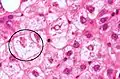

NASH (inflammation) and fibrosis stage 1

NASH (inflammation) and fibrosis stage 2

Lobular inflammation

NAFLD comprises two histological categories: NAFL, and the more aggressive form NASH. The presence of at least 5% fatty liver is common to both NAFL and NASH, but the features of substantial lobular inflammation and hepatocyte injuries such as ballooning or Mallory hyaline only occur in NASH. The majority of NAFL cases show minimal or no inflammation.[3][5][7] Pericentral and perisinusoidal fibrosis occur more often in adult-onset NASH, whereas portal fibrosis is more common in children with the disorder. NASH represents a more advanced stage of NAFL and is associated with poor outcomes such as cardiovascular events, cirrhosis, or hepatocellular carcinoma. ICD-11 does not use the term NAFL as it was deemed confusing with the family of disorders NAFLD. The preferred descriptions are instead: MAFLD without NASH or simple steatosis and "NASH". Also, the modifier with or without fibrosis or cirrhosis completes the diagnostic description.[3][7]

The primary characteristic of MASLD is the accumulation of lipids in the liver, largely in the form of triglycerides.[19] However, the mechanisms by which triglycerides accumulate and the reasons that accumulation can lead to liver dysfunction are complex and incompletely understood.[19][47][48] MASLD can include steatosis along with varied signs of liver injury: either lobular or portal inflammation (a form of liver injury) or ballooning degeneration. Similarly, NASH can include histological features such as portal inflammation, polymorphonuclear cell infiltrates, Mallory bodies, apoptotic bodies, clear vacuolated nuclei, microvesicular steatosis, megamitochondria, and perisinusoidal fibrosis.[16] Hepatocyte death via apoptosis or necroptosis is increased in MASH compared with simple steatosis, and inflammation is a hallmark of MASH.[32]